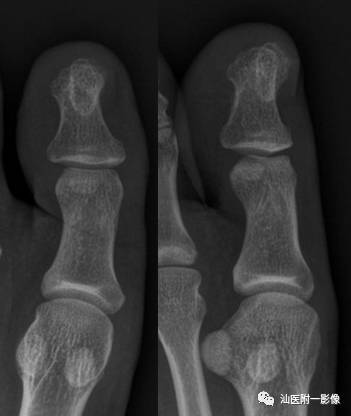

4.甲下外生性骨疣 (新增)

•一种累及远节指(趾)骨末端的骨软骨瘤样增生。

•最常累及踇趾,很少累及其他指(趾)骨。

•发病高峰10~30岁,男性多见。